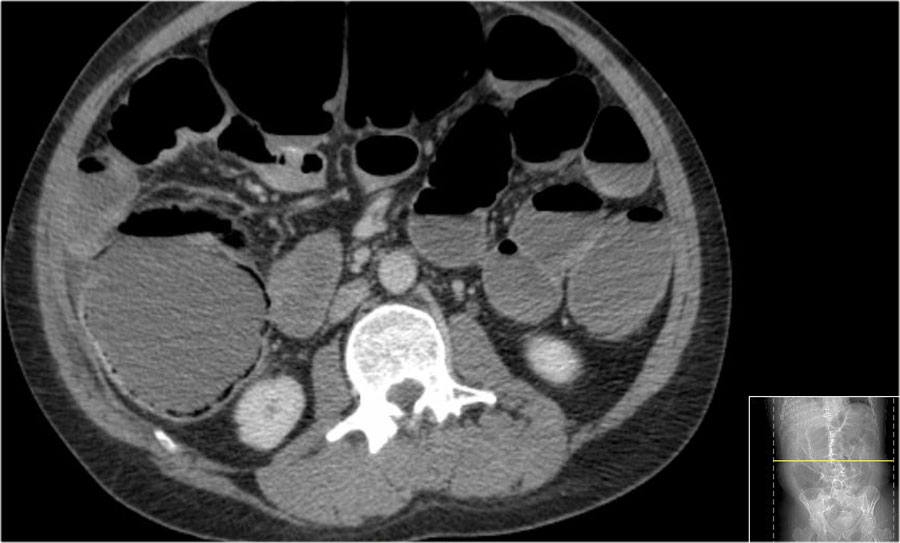

Ischemic Bowel with Air in Small Bowel Wall and in Portal Venous System Air In Colon Wall There are different terminologies in the medical. The presence of air in any portion of the gastrointestinal tract, from the mucosa to the mesenteric. Gas within the bowel wall is called pneumatosis intestinalis. Pneumatosis intestinalis (also called intestinal pneumatosis, pneumatosis cystoides intestinalis, pneumatosis coli, or intramural bowel gas) is. The most concerning pattern is gas within the bowel wall. Benign. Air In Colon Wall.

A CT image of dependent air in the bowel wall of Patient 1. Download Air In Colon Wall The most concerning pattern is gas within the bowel wall. The presence of air in any portion of the gastrointestinal tract, from the mucosa to the mesenteric. Gas within the bowel wall is called pneumatosis intestinalis. Pneumatosis intestinalis (also called intestinal pneumatosis, pneumatosis cystoides intestinalis, pneumatosis coli, or intramural bowel gas) is. Pneumatosis coli is a descriptive sign presenting radiographically. Air In Colon Wall.

CT scan of the abdomen with free air (star) and air in bowel wall Air In Colon Wall Benign causes of air in the bowel wall or pneumatosis intestinalis are multiple. The most concerning pattern is gas within the bowel wall. Gas within the bowel wall is called pneumatosis intestinalis. Pneumatosis coli is a descriptive sign presenting radiographically as intramural gas limited to the colonic wall. Pneumatosis intestinalis (pi) refers to the presence of gas within the wall. Air In Colon Wall.